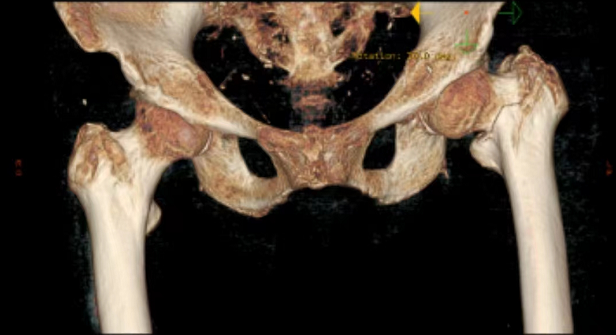

百岁老人在家不慎跌倒,随即出现左髋关节活动受限,不能活动。老人被家属带到当地县人民医院行左髋关节X线片检查示:左侧股骨转子间骨折(A2型)当地医院考虑患者年纪较大,身体条件差、手术风险高,不建议为患者行手术治疗。 患者听说焦作市第二人民医院骨科三区一位主任技术非常好,因此患者家属抱着试试的态度,带患者来我院救治,并以“左侧股骨转子间骨折”收住骨科三区。

入科后,陈旭副主任(副主任医师)认真评估患者身体条件,积极纠正电解质紊乱,考虑患者年纪较大,长期翻身困难,容易并发多种卧床并发症,因此患者入院第二天即积极安排患者手术。入院第三天,在余进伟主任(主任医师)的指导及麻醉手术部刘有才主任麻醉团队严密监控患者生命体征下,陈旭副主任医师为患者顺利施行手术。 术后患者生命体征稳定,随即转入骨科三区普通病房。陈豪杰医师作为管床大夫,积极进行术后处理,进行精准补液维持循环电解质稳定,定期多次查房关心患者恢复情况,发现问题立即处理。在李德荣护理团队个体化、细致化、规范化、科学化的精心护理下,患者慢慢恢复健康。术后第二天,患者在床上即可自如翻身、左髋关节自如活动,而且疼痛消失。术后第三天,在陪护的搀扶下离开病床进行排便,术后第十天,患者康复出院。于是,便出现了文章开头的一幕。这份“特殊”的医师节“礼物”,既是百岁老人及家属表达对医护人员的浓浓感激之情,更是对医院服务品质的认可和肯定,彰显出医患彼此间的信任与和谐,正是这份信任与和谐激励着我院医务人员,一如既往为患者康复做出最大努力! 股骨转子间骨折是最常见的髋部骨折,七十岁以上的人群发生率最高,一般由低能量损伤,如跌倒所致。股骨转子间骨折已经成为最重要的公共健康问题之一,尽管该部位血供丰富,骨折容易愈合,但老年患者大多合并内科疾病基础,长期卧床过程中容易引发各种并发症,如血栓栓塞症、坠积性肺炎、褥疮等,严重威胁着老年患者的生命健康,因此股骨转子间骨折又被称为“人生最后一次骨折”,此外患股骨转子间骨折的老年因髋关节活动受限,翻身及二便困难,增加了家属的护理难度,因此早期手术行股骨转子间骨折闭合复位髓内钉内固定术,已经成为了共识。术后老年髋部骨折即可获得稳定,出院方便居家护理,减轻老年患者痛苦,避免及减少因长期卧床造成VTE、坠积性肺炎以及褥疮等发生率。超高龄患者髋部脆性骨折,在严格评估手术风险及稳定生命体征,术后规范化、细致化的护理以及维持电解质、心肺功能稳定,尽可能的实现早手术!早康复!早出院!